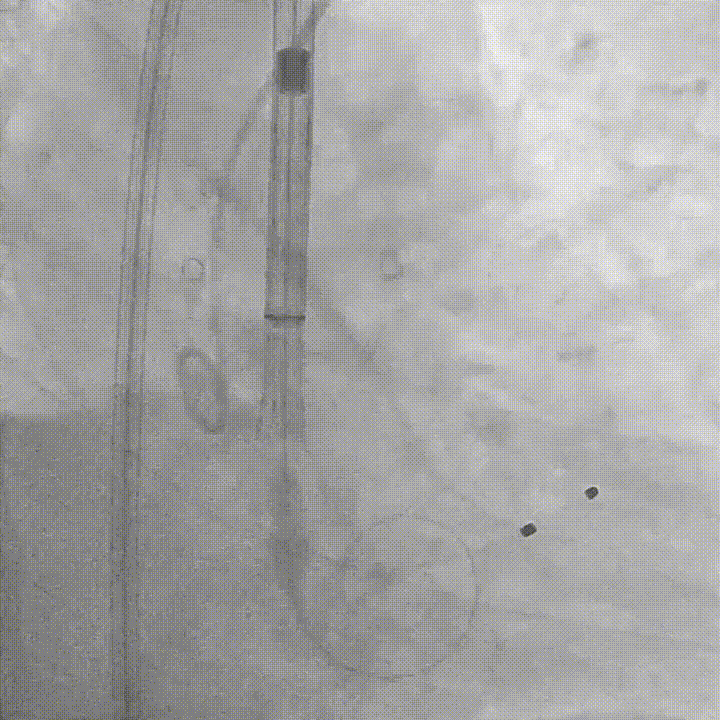

术前行右冠造影,发现存在多段管腔狭窄,血流受限,初步行球囊扩张以改善灌注,同时评估支架植入可能性;

右冠造影及球囊扩张